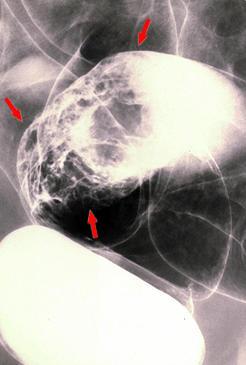

아유경성으로 점액생성이 강하게 나타난 융모종양(융모선종)

대장/S상

검사방법

X-P

종양의 최대경(밀리미터)

40이상